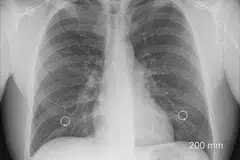

அப்போது அவரது நுரையீரலில் சிறிய பொருள் ஒன்று சிக்கி இருப்பது கண்டுபிடிக்கப்பட்டது. அது ஒரு தங்க மூக்குத்தியாகும்.

இதையடுத்து ‘ரிஜிட் பிராங்கோஸ்கோப்பி’ என்ற அதிநவீன அறுவை சிகிச்சை மூலம் அந்த மூக்குத்தியின் சிறிய பாகத்தை மருத்துவர்கள் வெளியே எடுத்தனர்.